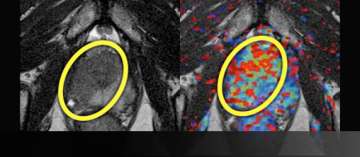

4) Example of Change to Nerve Sparing

Example of Change to Nerve Sparing

• 59 year-old

• PSA 4.3

• standard biopsy: 3+3=6 but large volume left